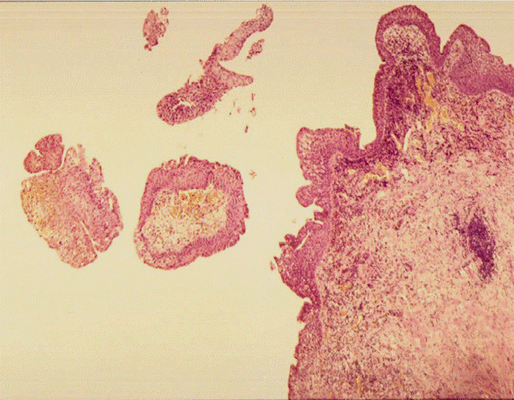

Патоморфологическая картина продемонстрирована на рисунке ниже.

Патоморфологическое исследование пациентка О.

Морфологическая картина полипоидного цистита с наличием гиперплазированного уротелия, признаков острого и хронического воспаления, реактивной уротелиальной атипии с множественными митозами, отеком собственной пластинки слизистой с фиброзом и полнокровными сосудами и полипоидными выпячиваниями. Окраска гематоксилин-эозином, х5

Патоморфологическое исследование пациента М.

Морфологическая картина полипоидного цистита. Окраска гематоксилин-эозином, х5

Патоморфологическое исследование пациента С.

Патоморфологическое исследование пациентки К.